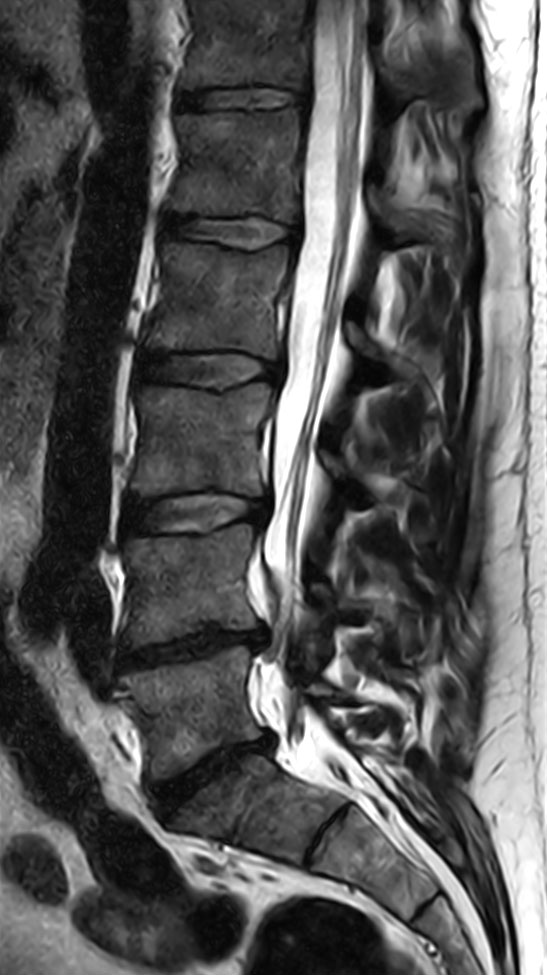

Patient with a lumbar spine bulging disc.

Sagittal T2w TSE